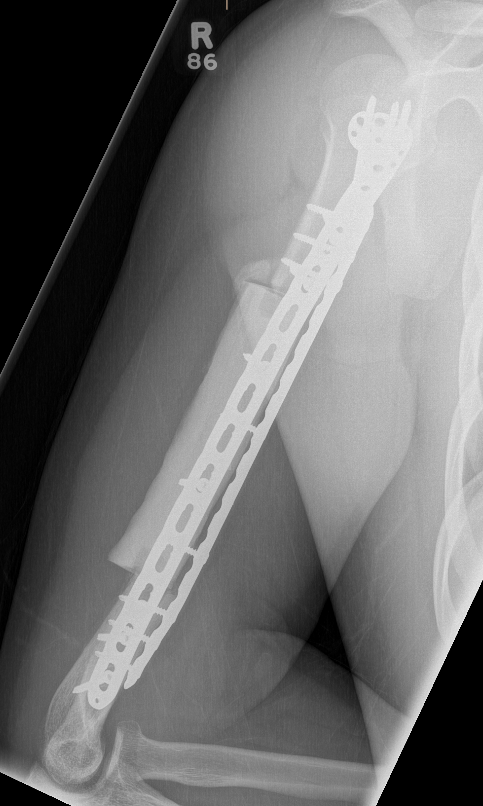

High grade / Wide resection

Wide resection